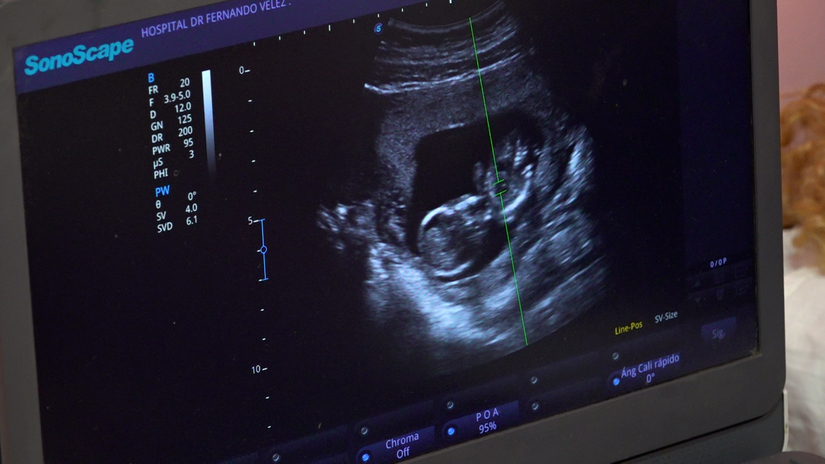

La doctora Judith García, directora del centro, comentó que a las mujeres se les realizan ecografías para evaluar la edad gestacional y el riesgo de presentar alguna anomalía congénita, preeclampsia o embarazo pretérmino.

“Estamos realizando estudios a mujeres entre las 11 y 13 semanas de embarazo, con una evaluación completa de su gestación, con un ultrasonido específico de tamizaje, en el cual se evalúan entre 100 y 150 embarazadas, provenientes de todo el departamento de Managua y del Silais-Managua”.